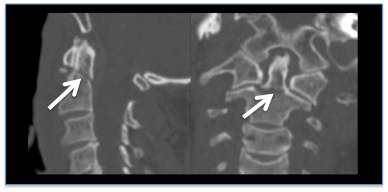

- TC de alta resolução da coluna cervical